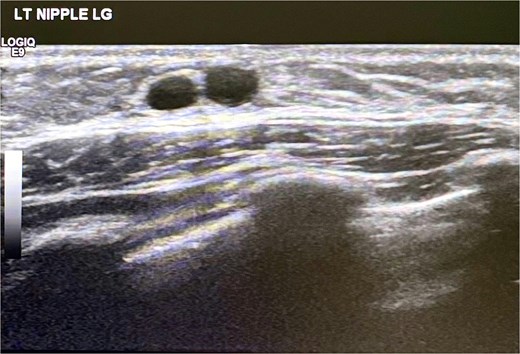

Targeted ultrasonography of the left breast was subsequently performed as the primary imaging modality. Sonographic evaluation demonstrated a small hypoechoic retroareolar lesion measuring ~10 by 2 millimeters with internal cystic ductal changes and absence of internal vascularity on color Doppler assessment. These findings were consistent with mammary duct ectasia and are illustrated in Fig. 1.

Ultrasound scan left breast showing cystic duct changes suggestive of mammary duct ectasia.